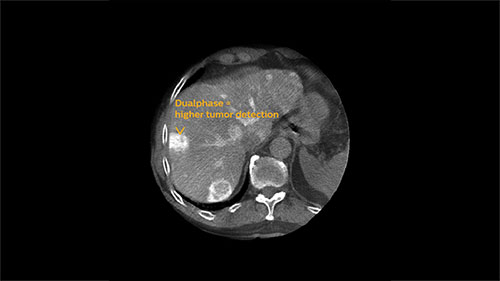

EmboGuide is based on XperCT Dual, a dedicated type of 3D oncologic imaging, which is used to visualize tumors and their feeding vessels.

XperCT Dual allows two phases of a contrast injection to be displayed next to each other. Clinicians can assess the feeder vessels to a tumor in the arterial phase and see the tumor boundaries in the delayed phase. Studies have shown that this novel method is superior to conventional DSA and provides equivalent imaging information to the gold standard of contrast enhanced MRI.³ ⁶

At the end of each procedure the dedicated oncologic imaging of XperCT Dual helps to determine the treatment endpoint in TACE for HCC.⁵ With XperCT Dual’s fast acquisition protocol, high resolution and soft-tissue contrast, a study has shown that its dual phase image information even correlates with the tumor response in the one-month follow-up MRI.

assess clinical image phase

Arterial phase

Delayed phase